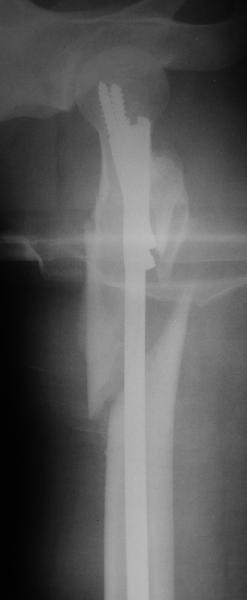

Фас

Оперировали вчера. Не сказать, что все прошло гладко - вертельная область была расколота и в сагиттальной, и во фронтальной плоскости, гвоздь попал в перелом и сместился кзади, что заметили уже после введения винтов, пришлось все извлечь и переставить. Снимки в приложении. Буду признателен за комментарии.